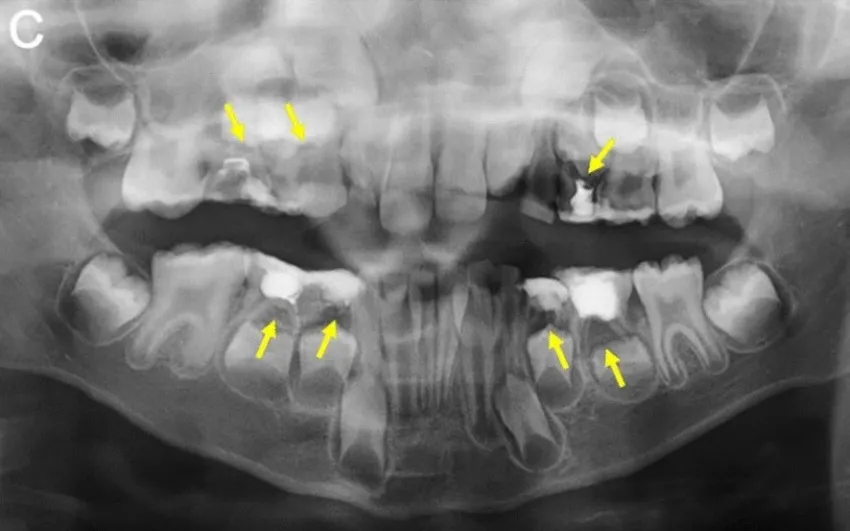

Badania kliniczne i radiologiczne w diagnostyce

W diagnostyce ropnia mózgu kluczowe są różne metody badawcze, które pozwalają na dokładne określenie obecności infekcji. Badania kliniczne obejmują szczegółowy wywiad lekarski oraz badanie neurologiczne, które pomagają w ocenie stanu pacjenta. Z kolei techniki obrazowania, takie jak rezonans magnetyczny (MRI) oraz tomografia komputerowa (CT), są niezbędne do wizualizacji zmian w mózgu. Te badania nie tylko umożliwiają zobaczenie ewentualnych ropni, ale również pomagają w ocenie ich lokalizacji oraz wielkości, co jest kluczowe dla dalszego postępowania.

Warto podkreślić, że wybór odpowiedniej metody diagnostycznej zależy od stanu pacjenta oraz dostępnych technologii. MRI jest szczególnie przydatne w identyfikacji zmian w tkance mózgowej, podczas gdy CT może być szybszą metodą w sytuacjach nagłych. Obie techniki mają swoje zalety i ograniczenia, dlatego lekarze często stosują je komplementarnie, aby uzyskać pełniejszy obraz stanu zdrowia pacjenta.